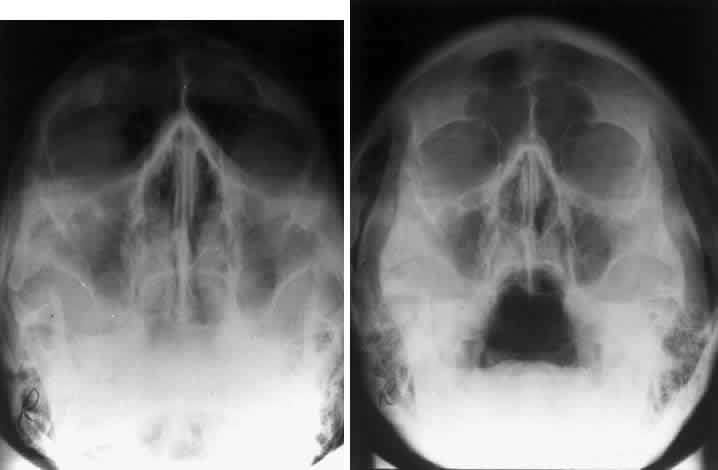

CALDWELL PROJECTION

In 1918 the evaluation of the frontal and ethmoid sinuses prompted Caldwell9 to describe a projection (Fig. 3) that eliminates the superimposition of the sphenoid bone on these paranasal sinuses. The patient is positioned with both the nose and forehead against the x-ray cassette while the x-ray beam is directed downward 15 degrees to 23 degrees to the canthomeatal line.5,6,9 This orientation also projects the petrous bones inferior to the orbit, thus avoiding obscuration of the orbital structures. As in the Waters view, the Caldwell view is a posterior-anterior projection. This excellent view of the frontal and ethmoid sinuses also allows good visualization of the orbital rims, greater and lesser sphenoid wings, lacrimal gland fossa, medial orbital wall, and both the superior and inferior orbital fissures.10 The innominate line is prominent in this view and represents the depression on the temporal surface of the greater wing of the sphenoid bone where it forms the medial wall of the temporal fossa or lateral wall of the orbit. This innominate line can be straight, end with a medial right angle turn, or continue inferiorly to form the outline of the pterygoid plate.8 A lack of continuity of the innominate line suggests a fracture of the lateral orbital wall.

Fig. 3. A. Schematic showing positioning for a Caldwell projection. (CM, canthomeatal line; CR, central ray) B. Radiograph of a Caldwell projection. The petrous ridge is positioned at the orbital floor. Detail of the orbital floor and maxillary sinus is blocked. C. The radiograph is taken at a steeper angle so the petrous ridge is now positioned lower within the maxillary antrum. (a, frontal sinus; b, innominate line; c, inferior orbital rim; d, posterior orbital floor; e, superior orbital fissure; f, greater wing of sphenoid;g, ethmoid sinus; h, medial orbital wall; i, petrous ridge; j, zygomatic-frontal suture; k, foramen rotundum) (A; Rao VM, Gonzalez CF: Plain film radiography and polytomography of the orbit. In Gonzalez CF, Becker MH, Flanagan JC [eds]: Diagnostic Imaging in Ophthalmology, pp 1–7. New York, Springer Verlag, 1986)